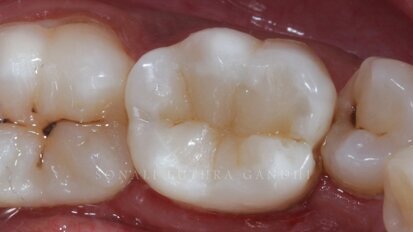

Cuspal layering technique to produce aesthetic posterior composite restorations – A case report

Composite resins have been the choice of restorative material for more than 20 years. Most clinicians have mastered the layering protocol for anterior teeth...